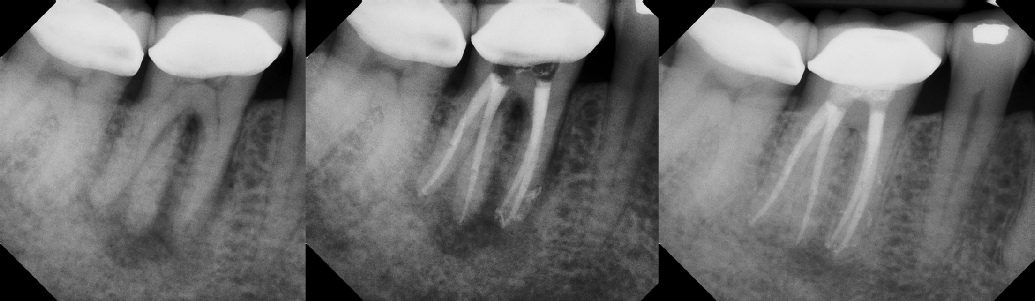

Pre-op Post-op 6 mos.